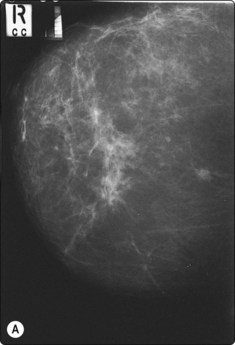

image

Fig. 3.5 FNA biopsy of a breast lesion with aggressive features

Several passes may be necessary to yield sufficient cells.

Many operators prefer US guidance for its speed, flexibility and real-time facilities. The patient is also able to lie comfortably during the procedure. The method is limited by the type of lesion; many microcalcifications are not visible on ultrasound examination. There is also the slight risk of pleural puncture or pneumothorax if used by inexperienced operators. The needle should run parallel to the chest wall and never be introduced perpendicular to the ribcage (see Fig. 3.4). By positioning the patient and compressing the breast, the depth of the lesion can be reduced. Breast lesions often require multiple sampling, typically best achieved using ultrasound guidance (Fig. 3.5).